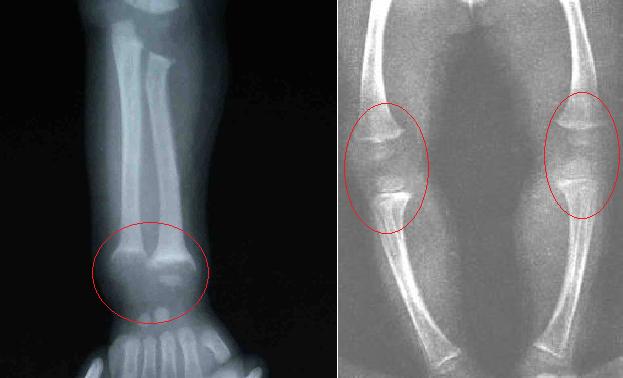

4、O形腿或X形腿

由于骨骼软化,婴儿爬行时可发生上肢弯曲,站立行走后则发生下肢弯曲。

另外,长骨骨骺端肥大,尤其是腕部、踝部,形成“手足镯”。

3、X射线检查

长骨发育较快,症状较明显,尤其是尺桡骨近腕关节处和胫腓骨近膝关节处最为明显。